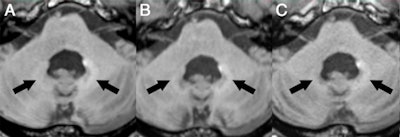

In the current retrospective study, Radbruch and colleagues narrowed their focus to possible evidence of signal intensity on unenhanced T1-weighted MR images in the dentate nucleus of patients who received an average of 23 injections of macrocyclic GBCAs.

A total of 33 patients were studied. All MRI scans were performed exclusively with 3-tesla scanners (Trio, Verio, Prisma, and Skyra, Siemens Healthineers) using the macrocyclic agents gadobutrol (Gadavist, Bayer HealthCare) and gadoterate meglumine (Dotarem, Guerbet). The mean injected dose per MRI scan was 7.74 mmol for gadobutrol and 12.61 mmol for gadoterate meglumine, based on the patient's body weight. There was an average of 12 weeks between every administration.

Signal intensity ratio differences were calculated based on dentate nucleus-to-pons and dentate nucleus-to-middle cerebellar peduncle (MCP) values by subtracting the signal intensity ratio of the first MRI scan from the signal intensity ratio at the last MRI exam. The mean interval between the first and last MRI scans was 273 weeks.

The researchers found no significant T1 signal increase in the dentate nucleus in any of the patients after a mean 23 serial injections of the macrocyclic GBCAs. The findings were reinforced by the dentate nucleus-to-pons ratio of -0.0032 ± 0.0154 (p = 0.248) and the dentate nucleus-to-MCP ratio of -0.0011 ± 0.0093 (p = 0.521).